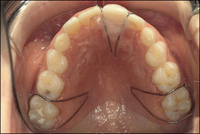

Giữ khoảng tháo lắp: Được chỉ định trong trường hợp mất nhiều răng trên cùng một cung răng, hàm lưu giữ được nhờ sự thích ứng tinh tế với niêm mạc và các móc. Ưu điểm của loại này là: thăng bằng cơ học, phục hồi được thẩm mỹ và phát âm, lập lại được kích thước dọc của khớp cắn, không cần thiết mài răng trụ, cho phép thực hiện các chức năng nắn chỉnh, có thể sửa chữa thích ứng với sự thay đổi của cung răng, dễ vệ sinh và không ảnh hưởng đến vệ sinh cung răng. Bên cạnh đó, hàm tháo lắp này vẫn còn một số nhược điểm như: gây vướng trong miệng, tác dụng phụ thuộc nhiều vào sự hợp tác của bệnh nhân, giá đắt, dễ bị mất và gãy vỡ, có thể cản trở sự phát triển. Do vậy hàm này được chỉ định trong trường hợp: mất nhiều răng, mất 2 bên răng hàm sữa thứ 1 và 2, thiếu răng trụ và mắc giữ không đủ.